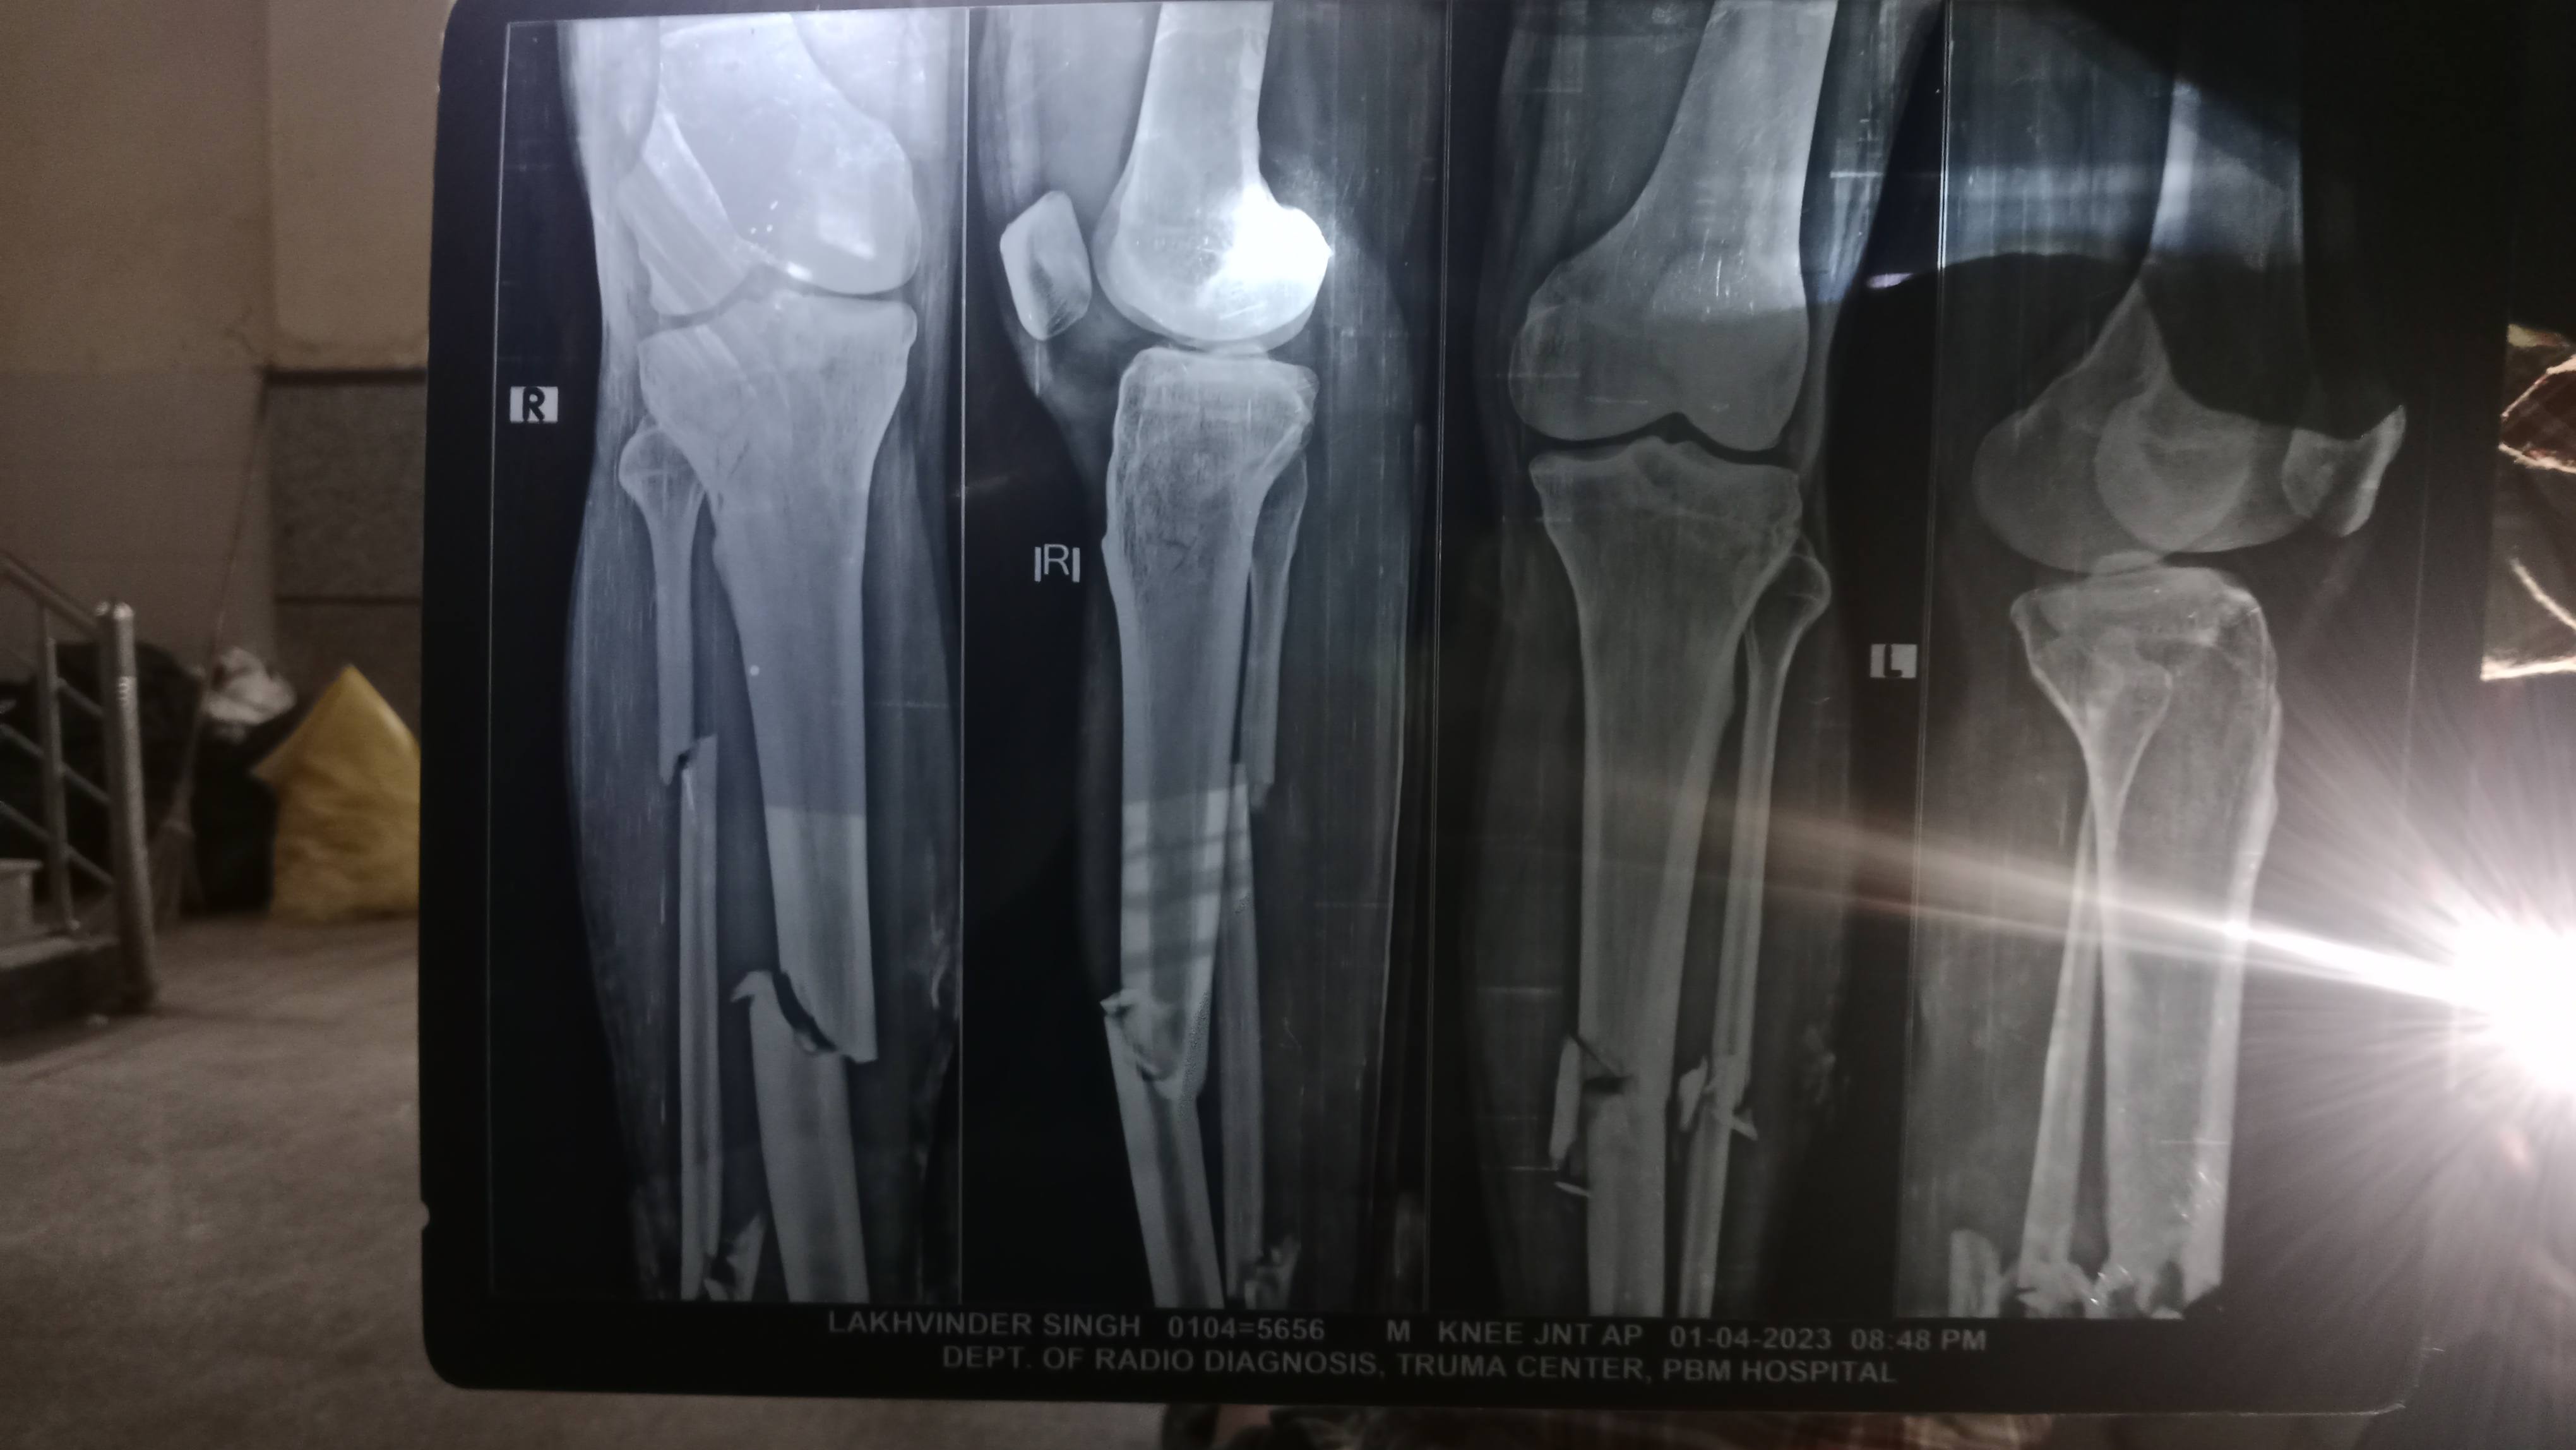

Lacking in rotational stability

Sir..I am 1 year post opreated for acl and meniscus... Done regular physio.....but it still feels little instablity while doing rotatory movements...feels pain on lateral and medial side of knee PLEASE HELP SIR...How can I overcome from this ....Thankyou..